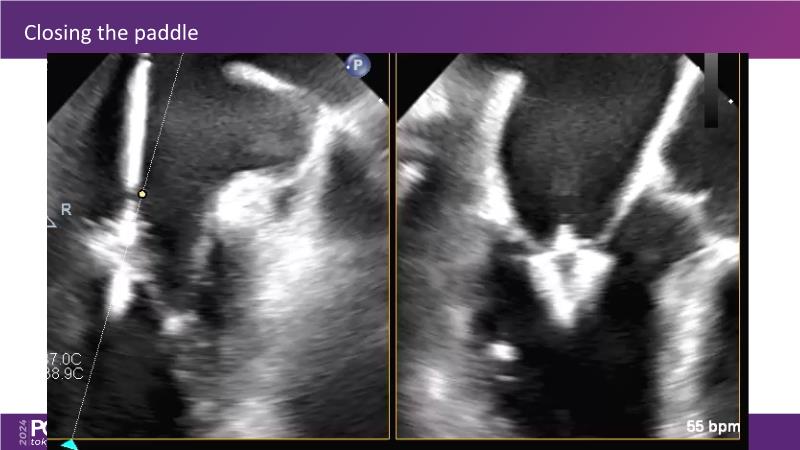

Watch this session to get an overview of a new TEER device, follow the step-by-step procedure related to initial experiences with this device for a Japanese patient with degenerative mitral regurgitation, learn about the latest data from RCT and registries, and follow discussions of challenging TEER cases!

- To learn procedural step-by-step of novel device